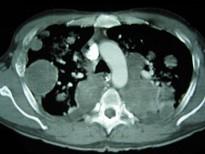

问题 33岁,男,咳嗽1周,有骨肉瘤病史,请结合胸片和CT图,选出最可能的诊断 ( )

选项 A.肺梗死 B.粟粒性肺结核 C.骨肉瘤转移 D.结节病 E.错构瘤

答案 C